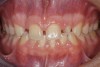

Fig 3. After resin-based composite bonding of the three incisors.

Figure 3

Once the teeth were bonded to ideal size, the "Maryland Bridge" was fabricated from a polyvinyl arch impression with the newly bonded teeth (Figure 3). The metal frame was cast from a non-precious alloy to allow for fabrication of a very thin frame and to create a better surface for bonding. After sandblasting the internal aspect of the frame with CoJet silica (3M ESPE), accomplishing salinization, and executing cementation with a dual-cure resin cement, a fairly good adhesion to the frame was anticipated.29 The enamel surface was etched with phosphoric acid for 30 seconds, the primer (Single Bond Plus, 3M ESPE) was applied to both the internal surface of the sandblasted framework and the etched enamel, and the bridge was cemented with RelyX ARC (3M Espe) dual-cured resin cement (Figure 4 and Figure 5).